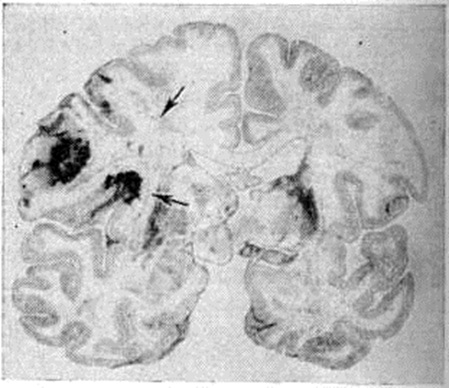

Геморрагический инсульт, как правило, возникает при заболеваниях, протекающих с повышенным артериальное давление. Это обусловлено тем, что сосудистые кризы (смотри полный свод знаний), характерные для гипертонической болезни (смотри полный свод знаний) и артериальной гипертензии (смотри полный свод знаний Гипертензия артериальная), приводят к морфологический изменениям стенок внутримозговых сосудов с нарушением их проницаемости — плазматическому пропитыванию (рисунок 1), некрозам (рисунок 2), образованию микроаневризм (рисунок 3) и их разрывам. Разрыв врождённых артериальных и артериовенозных аневризм может протекать на фоне нормального давления. Преимущественная локализация и характер геморрагий определяются особенностями ангиоархитектоники различных отделов мозга. При гипертонической болезни наиболее тяжёлым изменениям подвергаются сосуды подкорковых узлов и зрительного бугра. Это объясняется отхождением глубоких ветвей под прямым углом от средней мозговой артерии, являющейся продолжением внутренней сонной артерии, и незначительным числом анастомозов сосудов в этой области. В связи с этим на вскрытии кровоизлияния наиболее часто (40%) обнаруживаются в подкорковых узлах с распространением в прилежащее белое вещество (так называемый латеральные кровоизлияния, то есть расположенные латерально от внутренней капсулы, рисунок 4). Второе место по частоте (16%) занимают обширные кровоизлияния, разрушающие подкорковые узлы, внутреннюю капсулу, зрительный бугор (так называемый смешанные кровоизлияния — рисунок 5). Кровоизлияния в зрительный бугор (так называемый медиальные — рисунок 6) составляют 10%, в мозжечок — 6—10%, в мост мозга — 5% от общего числа внутримозговых геморрагий. Кровоизлияния только в белое вещество полушарий мозга встречаются крайне редко. Подразделение полушарных кровоизлияний на латеральные, медиальные и смешанные имеет особое значение в связи с хирургическим лечением геморрагического Инсульт.

Рис. 4.

Фронтальный срез головного мозга на уровне зрительных бугров с «латеральным» кровоизлиянием (стрелкой указана гематома) в левом полушарии мозга.